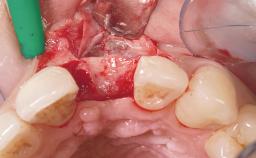

Immediate Placement of an Implant in a Maxillary Right Central Incisor Site

A 30-year-old female patient was referred to the office for the treatment of tooth 11. Her chief concern at the initial visit was to inquire, “Why is my tooth pink?” Upon clinical examination, it was determined that tooth 11 had a previous history of trauma and that the clinical crown had become noticeably pink in color as a result of internal resorption. This diagnosis was confirmed radiographically, indicating a large radiolucency involving the central and distal portions of the clinical crown. It was determined that restoration of this tooth was not possible, and that extraction was indicated. The presence of a mid-line diastema, which the patient wanted to reproduce, directed the treatment plan for tooth replacement utilizing a dental implant.

Bone Augmentation Horizontal|Simultaneous

Augmentation Materials Autogenous chips|Membrane

Placement Protocol Immediate implant placement

Socket Integrity Sufficient, with intact bone walls

Bone Volume Sufficient, with intact walls